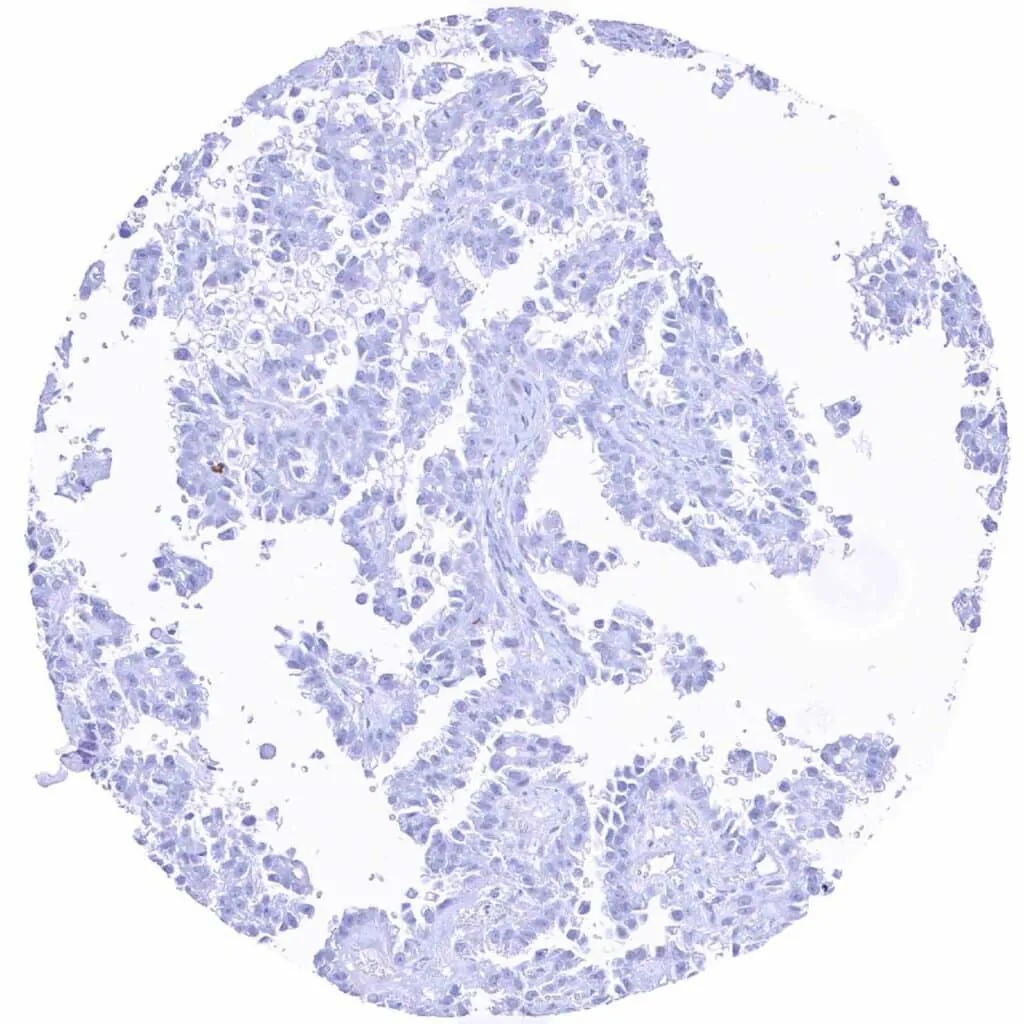

Urinary bladder – MYH7 negative non-invasive papillary urothelial carcinoma (pTa G2_ low grade)